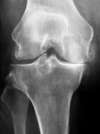

arthrose interne du genou sans déformation osseuse du squelette : traitement chirurgical par pose de prothèse partielle (Prothèse Unicompartimentaire Interne)